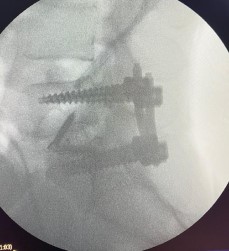

La Cirugía ALIF es una técnica de fusión lumbar anterior que permite acceder a la columna desde el abdomen (vía anterior), sin intervenir la musculatura dorsal. Se realiza una discectomía y se coloca un espaciador intersomático (cage) con injerto óseo para estabilizar la columna y corregir deformidades, preservando los músculos y reduciendo el traumatismo quirúrgico.

Permite el uso de implantes de mayor tamaño, restaurando la altura discal y la alineación sagittal con alta tasa de fusión.

Proceso de fusión completado en un período de hasta 12 meses, con seguimiento radiológico.